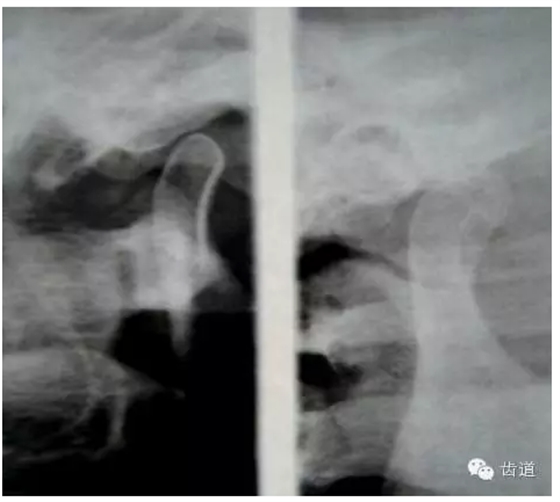

3.關(guān)節(jié)造影 主要是上腔造影

— 顯示關(guān)節(jié)盤移位,穿孔。